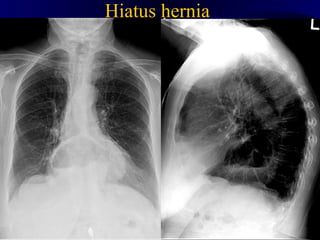

Hiatus hernia

hh